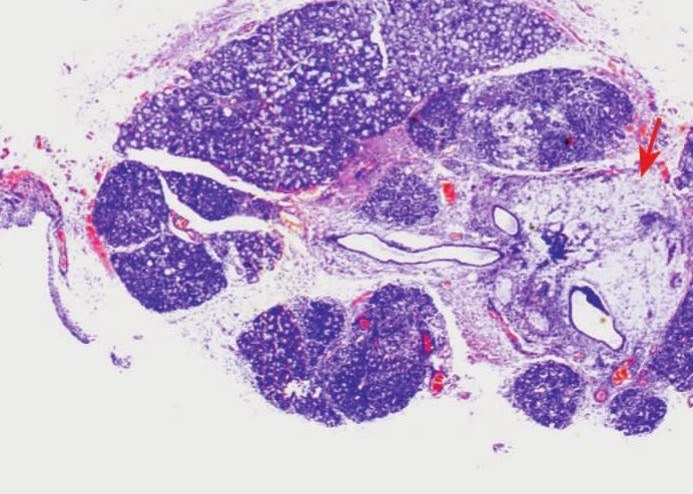

此外,对比两组患者在RAI治疗后唾液腺功能变化情况可以发现,两组患者双侧腮腺MSP变化值有显著差异,提示与补硒组相比,对照组在RAI后双侧腮腺MSP显著降低。从两组患者中典型病例的闪烁扫描结果也可以看出,补硒对于DTC患者RAI治疗引起的唾液腺功能损伤有保护作用。